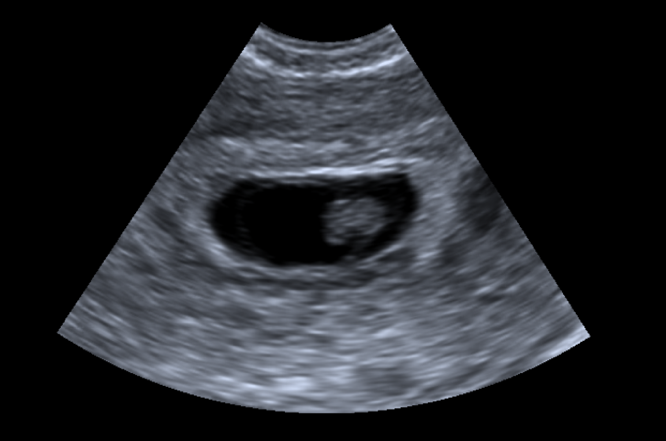

• Ultrasound: Absence of fetal heartbeat or movements, or an empty gestational sac in early pregnancy.